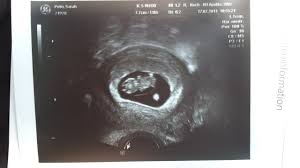

Den ersten Ultraschall hatte ich vaginal und der Zweite war dann über den Bauch. SSW lassen sich auf dem Ultraschallbild inzwischen Zehen erkennen. Auch die Arme sind deutlich gewachsen und biegen sich bereits an den Ellenbogen.

Der Arzt misst dabei das Gewicht der Schwangeren und den Blutdruck. Die ersten Vorsorgeuntersuchungen stehen an. Zwischen Händen und Armen zeichnet sich das Handgelenk ab und an den Füßen bilden sich die Schwimmhäute zurück sodass die Zehen sichtbar werden.

Der Kiefer ist nun entwickelt. Langsam sieht es auch wie ein richtiges Baby aus. Die Beine sind länger geworden und in der 9.

Die Beine sind länger geworden und in der 9. Mit der ersten Vorsorgeuntersuchung in der 9. Auch die Nasenöffnung und die Ohren sind in der 9.

SSW gut zu erkennen genauso wie die Oberlippe und eine starke Pigmentierung der Augen. Das Baby schlägt nun Purzelbäume zappelt und schwimmt in der Fruchtblase.